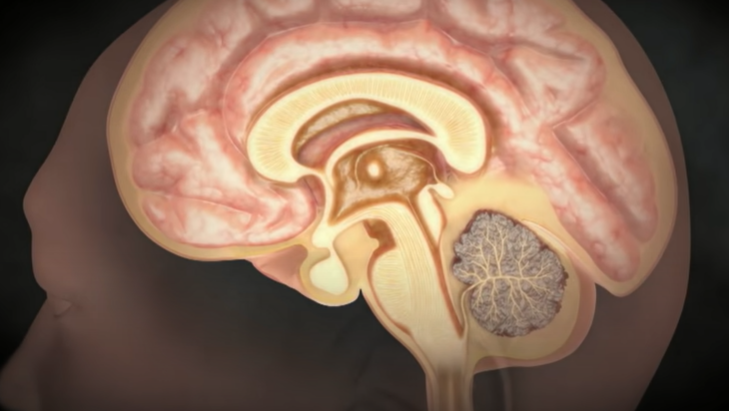

두통을 유발하는 뇌질환

1. 뇌혈관에 불룩하게 솟은 뇌동맥류가 터지거나,

2. 혈관벽이 찢어지면서 뇌졸중을 일으키는 박리성 뇌동맥류

3. 그리고 뇌종양의 흔한 증상 역시 두통이다.

뇌동맥류

약해진 혈관 벽이 늘어나 마치 꽈리 모양으로 부풀어 오른 뇌동맥류는 터지는 순간 극심한 두통을 유발한다.

가장 위험한 게 뇌동맥류 파열에 의한 지주막하 출혈이다. 처음 출혈이 생기고 두통이 어느 정도 해소된 다음에는 환자가 마치 병이 나은 것처럼 생각하는데 만약 뇌동맥류가 터진 상태로 출혈이 멈추지 않으면 급사를 하게 된다.

- 신경외과 김종수 교수

뇌에 있는 동맥은 지주막하 공간이라는 뇌척수액이 가득 차 있는 곳에 있어서 마치 물에 동맥이 떠 있는 형태이다. 그곳에 있는 동맥류에 꽈리가 생겨서 파열되면 뇌 전체로 피가 퍼지기에 순식간에 뇌압을 상승시킨다. 뇌동맥류가 터지는 정도에 따라서 임상적으로 등급을 나누는데 한두 시간 정도 참을 수 있을 정도의 가벼운 두통부터 급사하는 정도까지, 출혈량이나 파열 정도에 따라 다양한 임상 증상이 생긴다.

- 신경외과 김종수 교수

목덜미에서 머리까지 아프기 때문에 '고혈압인가? 목 디스크인가?' 생각하는 경향이 있다. 그것도 어느 순간이 지나면 특징적 통증이 없어지고 약한 통증만 있어 구별을 잘하지 못하는데, 뇌동맥류가 파열돼서 가벼운 뇌 지주막하 출혈이 발생해도 두통이 특정 시점에 갑자기 생긴다. 이것이 매우 중요하다. 또한, 급작스럽고 평생 경험해보지 못한 정도의 굉장히 심한 두통이 오게 된다. 망치로 뒤통수를 세게 때리는 정도로 심한 두통이 갑작스럽게 오는 것이 특징이다.

- 신경외과 김종수 교수

뇌척수액 누출로 인한 두통

뇌척수액이 척추 어디에선가 새어 빠져나가게 되면

그 위에 떠 있던 뇌가 아래로 주저앉으면서 심각한 두통을 유발한다.

물주머니에 뇌가 담겨 있다고 생각하면 된다. 물이 150cc 정도 있는데 그 안에 1.4kg 정도의 뇌가 떠 있다고 보면 된다. 이 무게를 실제 못 느끼는 것은 부력 때문인데, 물 주머니가 새는 경우가 있다. 그러면 물이 빠지면서 부력이 없어지니까, 뇌가 주저앉으면서 심한 두통을 일으킬 수 있는 것이다. 고통지수 10이라고 하면 10점 이상의 도통이라고 할 수 있다. 특징은 서있을 때는 척수액이 빠지기 때문에 굉장한 통증을 유발하는데, 누우면 최대 1분 내로 두통이 없어진다. 그러나 다시 일어나면 척수액이 더 빠지고 뇌가 밑으로 처지면서 극심한 통증이 재발한다.

혈관 기형이 있다거나 혈전이 생겨서 혈관이 부풀어 오른다든지, 특히 정맥에 혈전이 생기면 두통이 심하게 나타날 수 있고, 또 하나는 머리 안쪽에 염증이 생기는 경우로서 뇌막염, 수막염, 뇌염, 결핵성 내막염이 있다. 또는 뇌압이 너무 올라가거나 떨어지면 심한 두통이 올 수 있다. 뇌압을 올리는 것은 뇌종양이 있다. 뇌에는 물이 있어 물을 만들어 내는 것이 너무 과다하거나 하루 3번 순환해야 하는데 물의 순환 과정이 막혀 물이 빠져나가지 못하는 경우에는 수두증이 생긴다.

- 신경과 정진상 교수